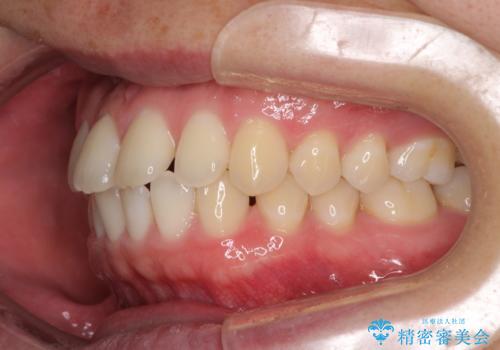

すきっ歯の改善 インビザライン矯正治療

- 上の前歯の隙間を気にして来院された患者様です。

インビザラインにより、上下の歯列を側方に拡大しつつ、前歯の隙間を閉じていくこととしました。

1日22時間の装着時間をしっかりと守ってくださったので、隙間がきれいに閉じ、口元の突出感も改善することができました。